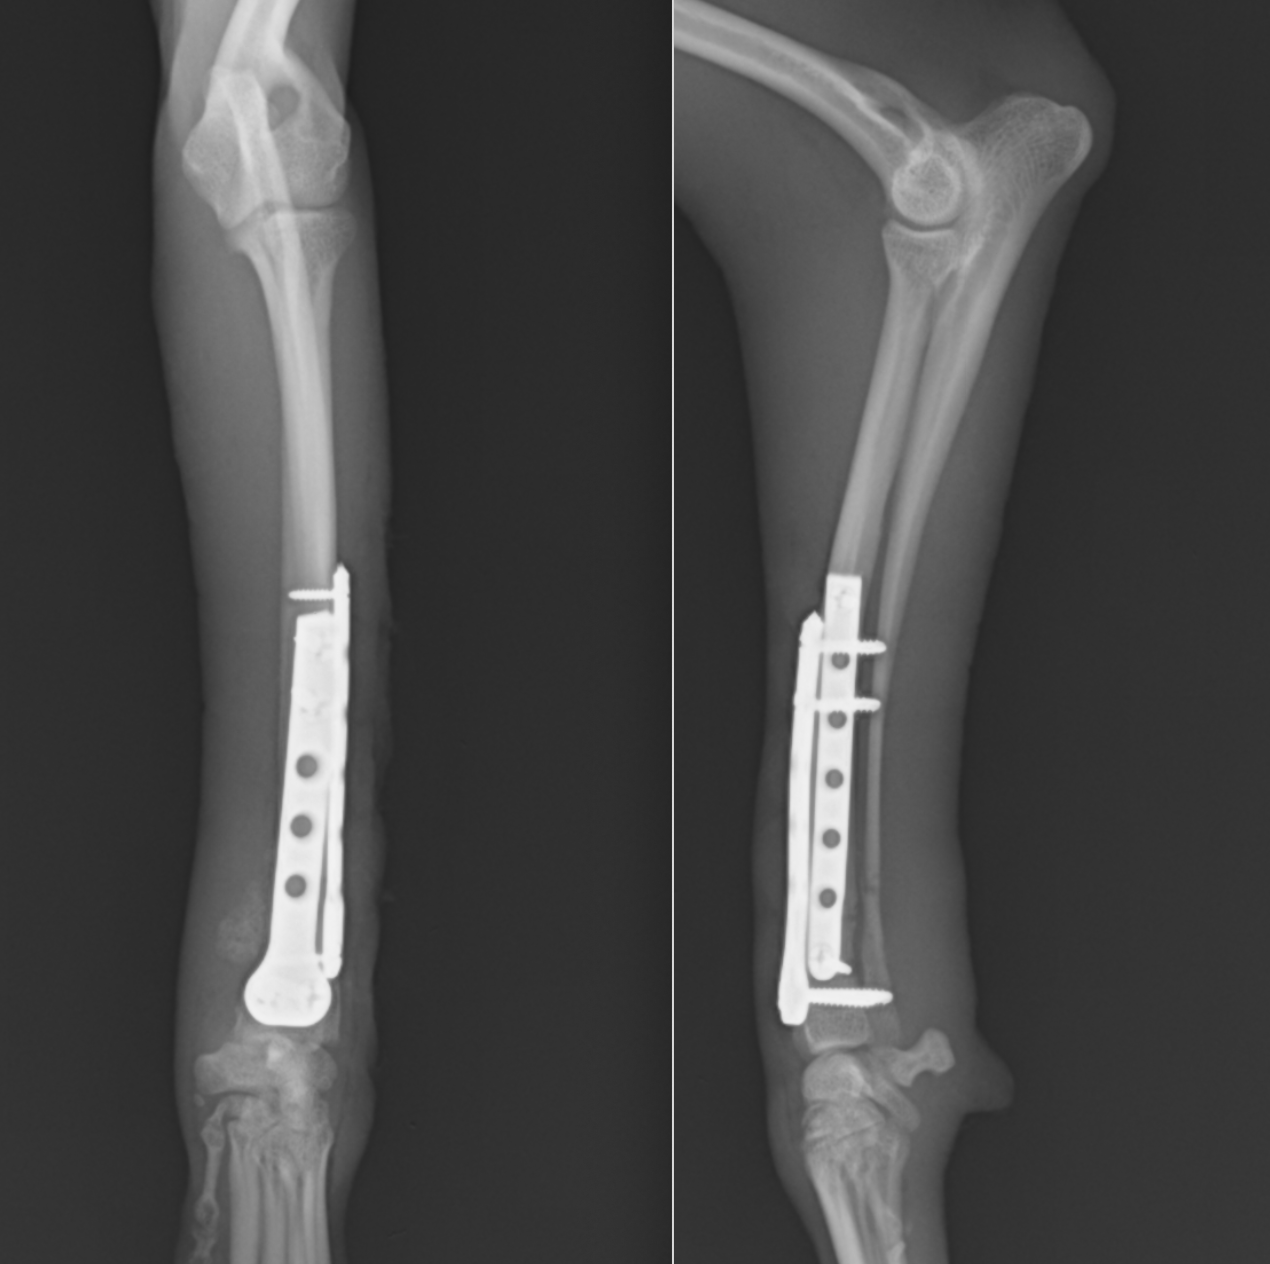

術後レントゲンです。橈骨全域に渡ってプレートが入っています。近位は少し外側に曲がっているため、最初からプレートを曲げています。術後2日目には患肢を使っての歩行が可能でした。また、キャスト(ギプス)も使わないので、ストレスなく生活が可能です。術後1ヶ月半ほどで正面のプレートを抜去しています。

この子もプレートが破綻して2回めの手術をしているため、プレートが長くなっています。

術後経過は順調で2ヶ月ほどで正面のプレートを抜去しました。